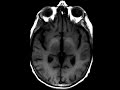

Hepatic Encephalopathy

This case demonstrates an incidental finding in a patient with known chronic hepatic encephalopathy. We see increased intrinsic T1 signal within the basal ganglia, particulary the globi pallidi, as well as extending into the cerebral peduncles of the midbrain, likely reflecting abnormal maganese deposition secondary to portosystemic shunting.